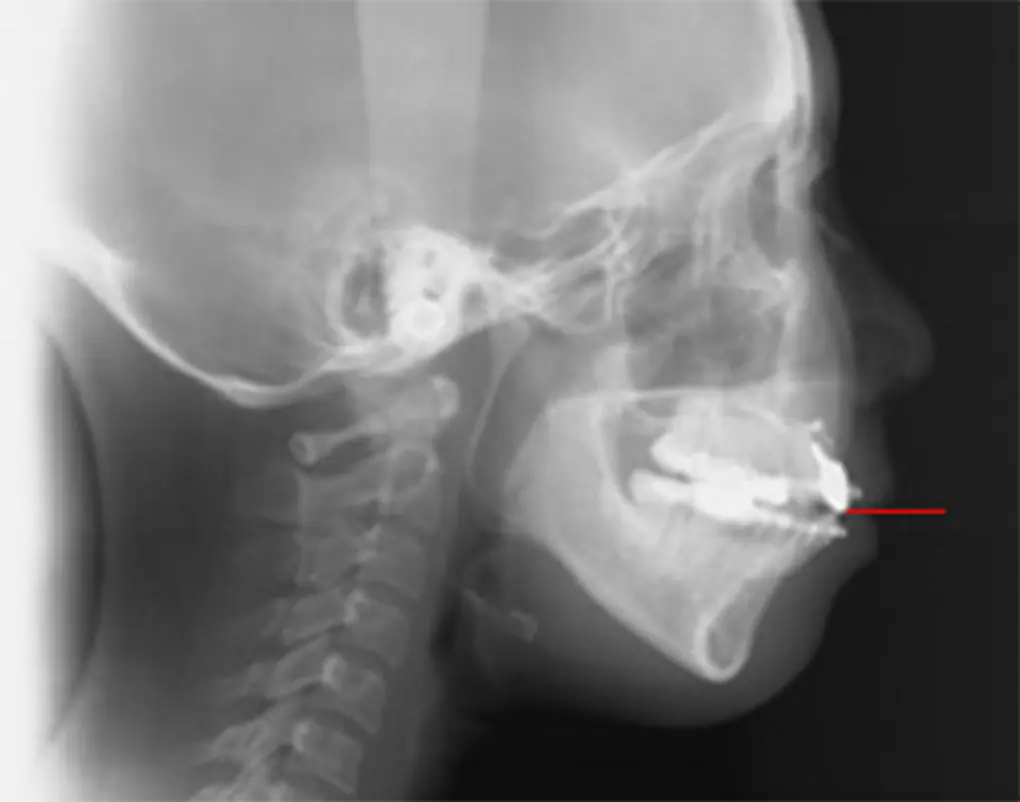

歯列全体を上方へ引き上げることで、改善を図ります。

今までは外科手術が必要な症例でしたが、歯科矯正用アンカースクリューを使うことで、多くの症例が外科手術せずに改善が見込めます。

奥歯を下に引っ張ります。

今までは、取り外せるゴムや通常の矯正装置とは違う装置を別途、長期間使う必要がありました。しかし、奥歯を歯肉の方向に埋め込むことで、顎が関節を中心に回転し、前歯が噛むようになります。